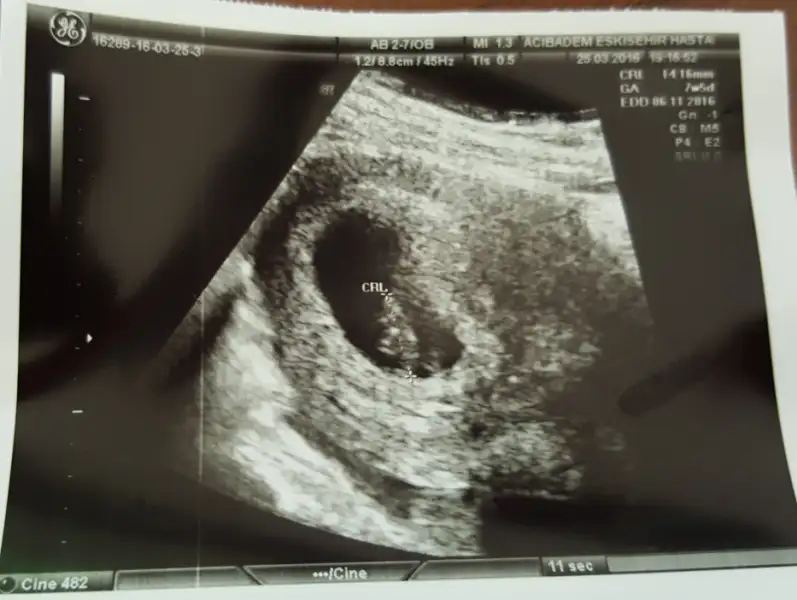

kizlar ilki 9 haftalik ikincisi 10 haftalik fotografi :)) sizce hala erkek mi dusunceniz :))

dlrsordn dlrsordn burda tam 6 haftalik bana da yorum yapar misn?